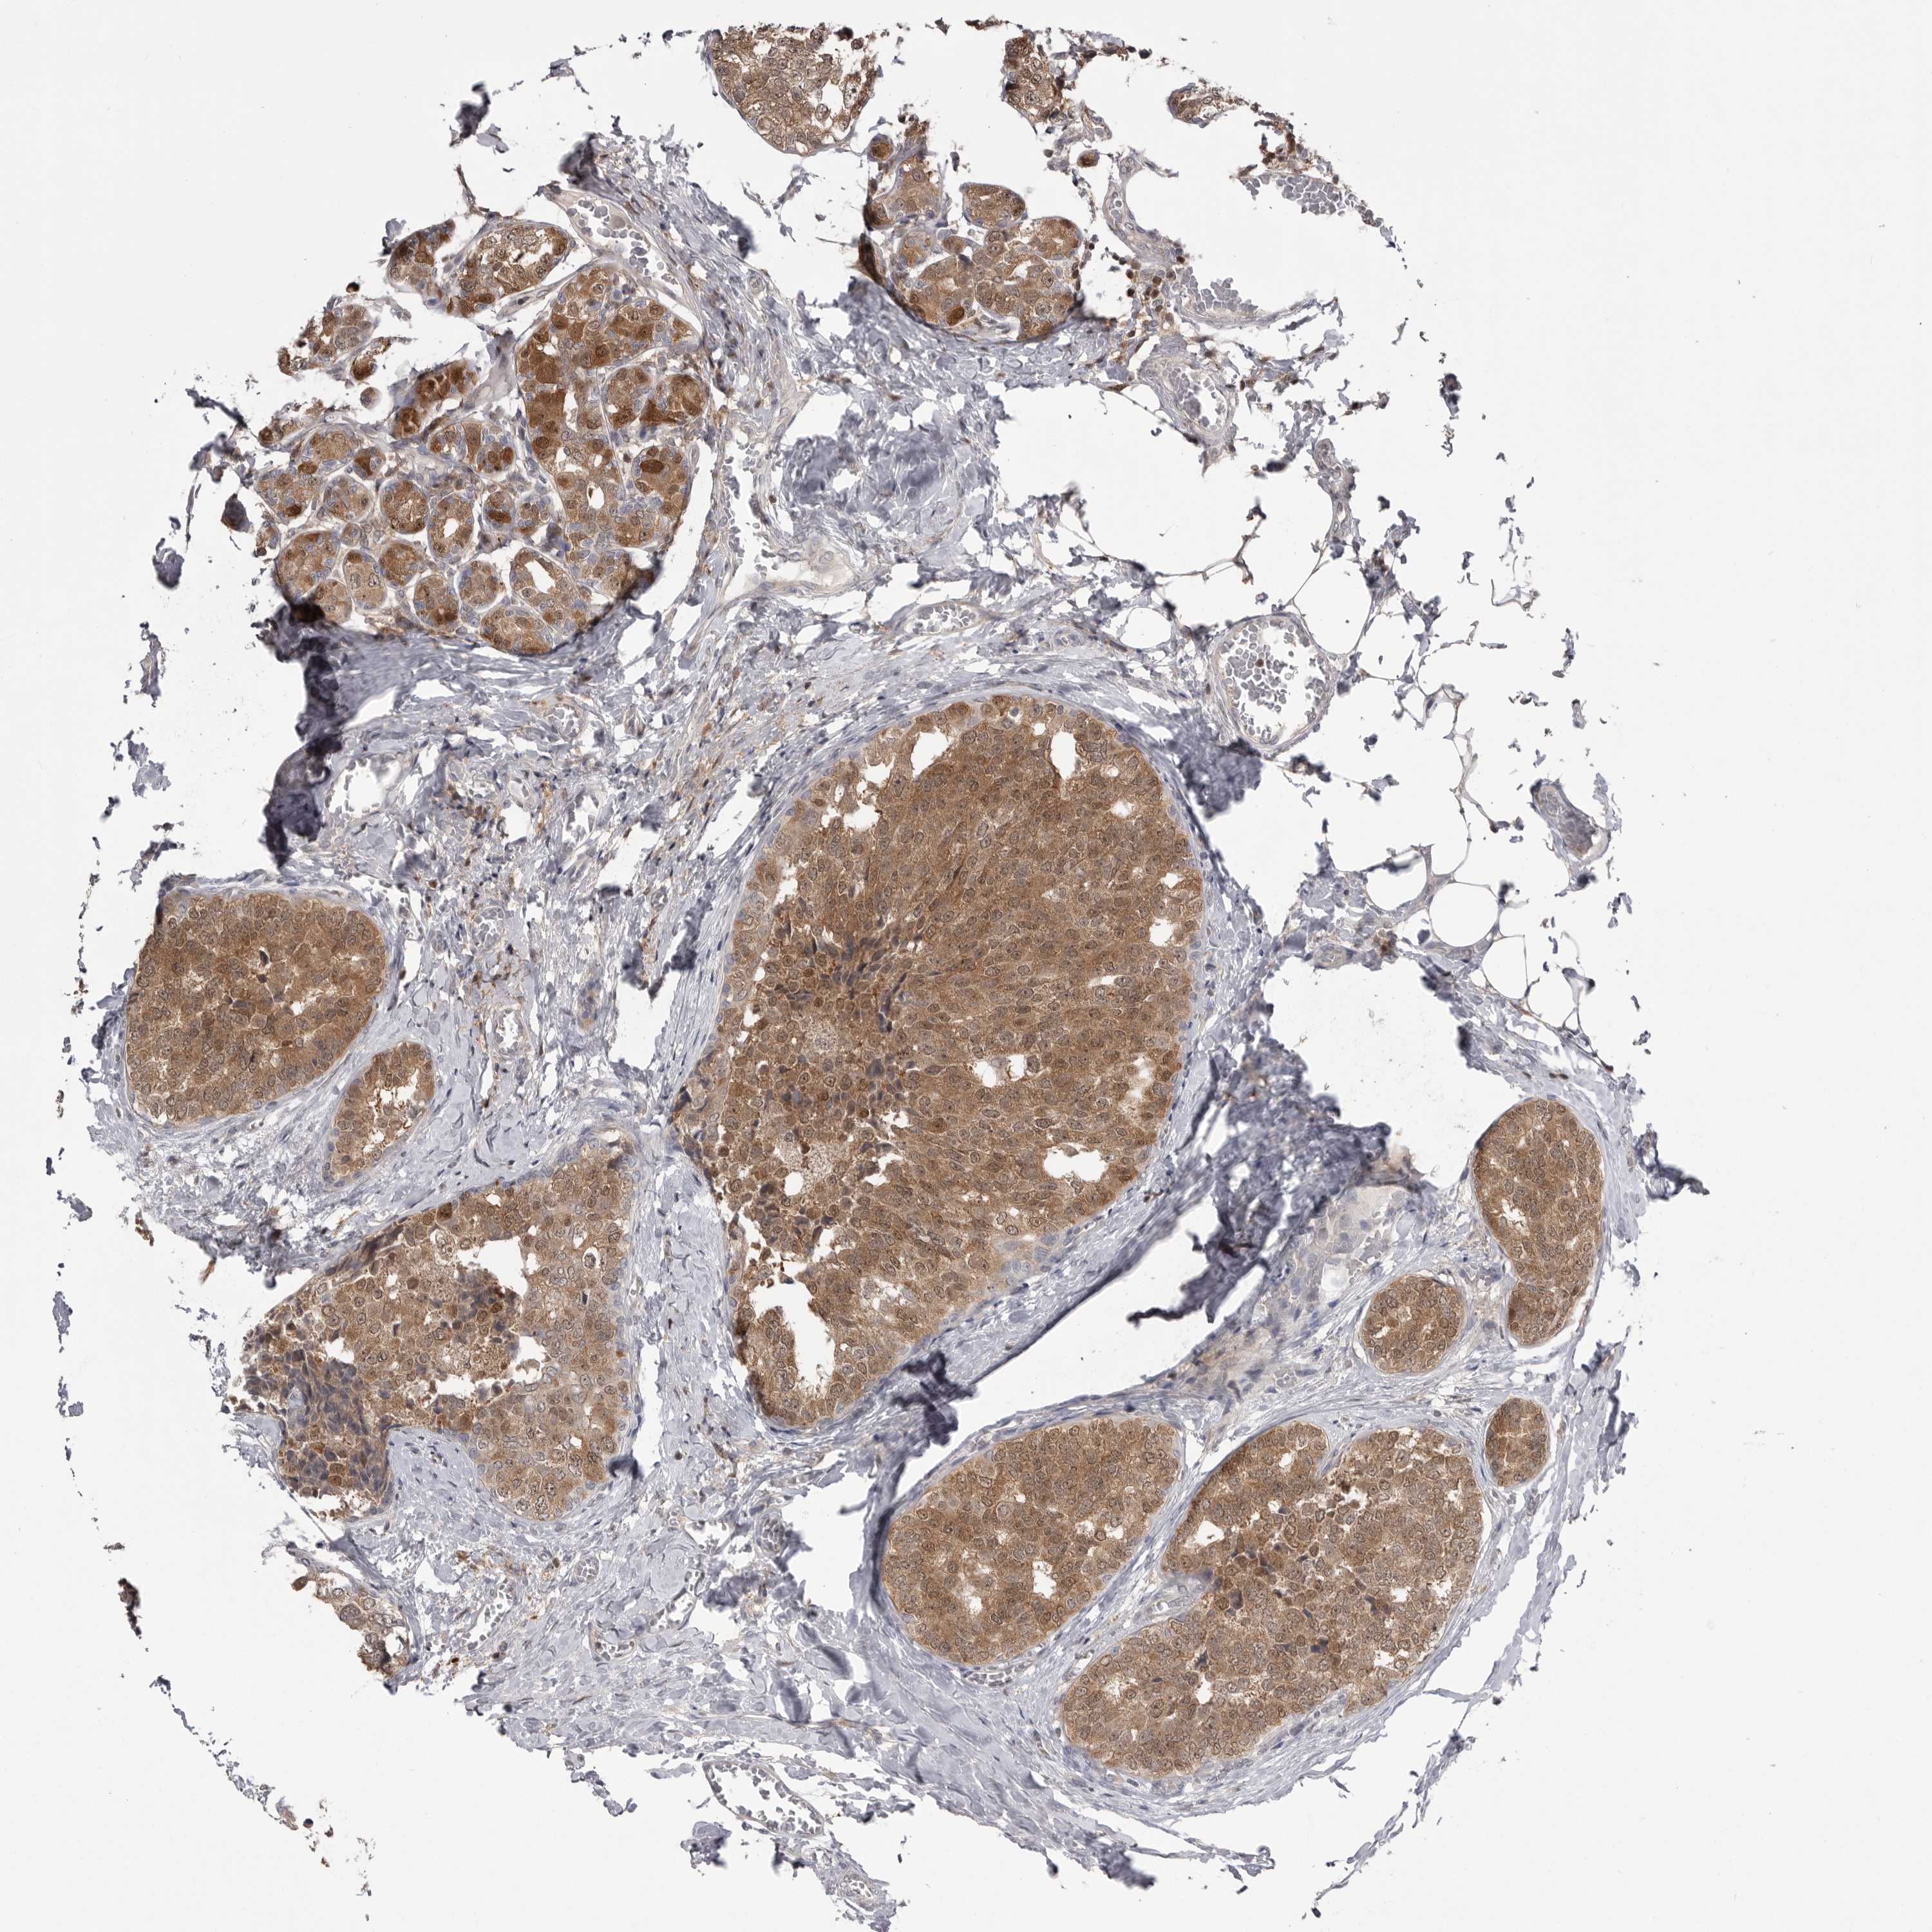

BRCA TCGA BRCA VALIDATION PROTEIN EXPRESSION